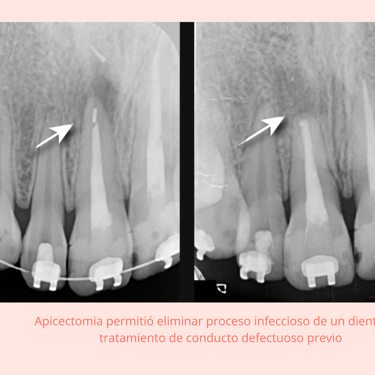

Importancia: La apicectomía es un procedimiento quirúrgico que se realiza cuando el tratamiento de conducto no es suficiente para eliminar una infección .Es esencial para eliminar la infección y prevenir su propagación.

La apicectomía es un procedimiento quirúrgico utilizado cuando una infección persiste en el extremo de la raíz del diente después de un tratamiento de conducto. Este procedimiento implica la remoción del extremo de la raíz y del tejido infectado circundante.

Resultados esperados: Eliminación de la infección crónica y conservación del diente, con una alta tasa de éxito a largo plazo.